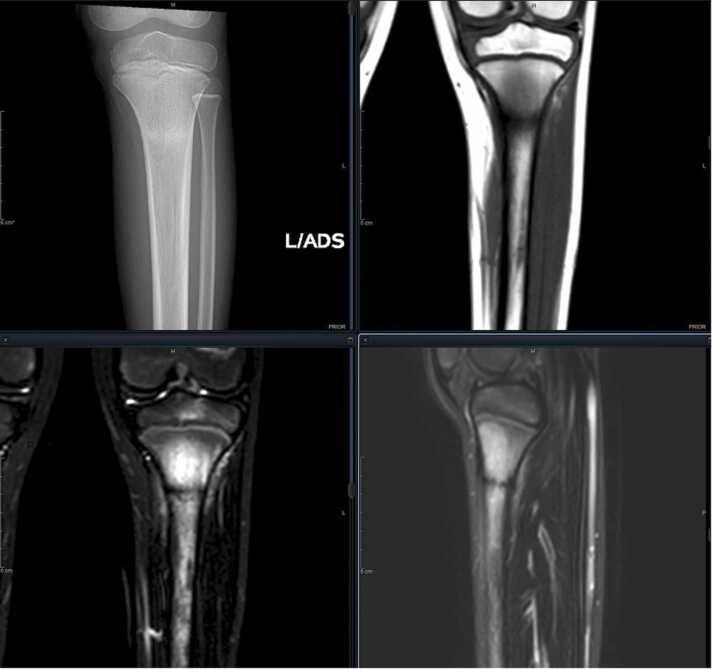

儿童和青少年的应力性骨折与过度使用损伤

Stress fractures and overuse injuries in children and adolescents.

There is an intricate connection between physical activity, bone health, and the susceptibility to stress fractures and overuse injuries. Physical activity has a positive impact on bone strength while a sedentary lifestyle can lead to a heightened risk for injury. The rise of early sports specialization has led to a substantial increase in overuse injuries, particularly in individual sports.Bone Stress Injuries (BSI) represent a category of overuse injuries closely linked to single sport specialization. BSI involves a spectrum of altered bone mechanics, ranging from edema of periosteum, endosteum, and bone; potentially leading to partial or full cortical breaks. This condition is prevalent in high-level athletes and encompasses stress reactions and fractures, resulting from an imbalance between injury creation and repair. Up to 20% of adolescents are affected, with the tibia being the most common location, predominantly occurring in athletes aged 15 to 25. A holistic approach integrating both physical and nutritional aspects is warranted to ensure sustained musculoskeletal health across diverse pediatric and adolescent groups and athletic endeavors.

身体活动、骨骼健康以及应力性骨折和过度使用损伤易感性之间存在复杂的联系。身体活动对骨骼强度有积极影响,而久坐不动的生活方式会增加受伤风险。早期运动专项化的兴起导致过度使用损伤大幅增加,尤其是在个人运动项目中。骨应力损伤(BSI)是一类与单一运动专项化密切相关的过度使用损伤。BSI涉及一系列改变的骨力学,范围从骨膜、骨髓膜和骨骼的水肿;可能导致部分或完全皮质断裂。这种情况在高水平运动员中很普遍,包括应力反应和骨折,是由损伤产生和修复之间的不平衡导致的。高达20%的青少年受到影响,胫骨是最常见的部位,主要发生在15至25岁的运动员中。需要一种综合身体和营养方面的整体方法,以确保不同儿科和青少年群体以及体育活动中的肌肉骨骼健康持续良好。

Retrospective Review of Radiographic Imaging of Tibial Bony Stress Injuries in Adolescent Athletes With Positive MRI Findings: A Comparative Study.回顾性分析 MRI 阳性的青少年运动员胫骨骨应力性损伤的影像学表现:一项对比研究。

Sports Health. 2023 Mar-Apr;15(2):244-249. doi: 10.1177/19417381221109537. Epub 2022 Aug 2.